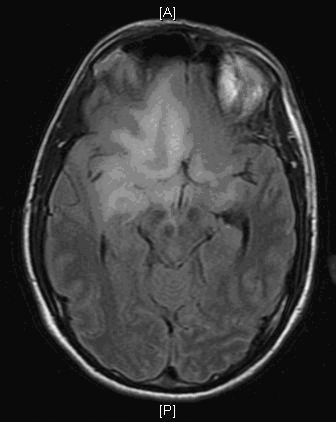

Clinical information: The patient was a 40 year-old man with a history of headache for months and suddenly develop nausea and vomiting in the morning. MRI demonstrated a diffusely infiltrative, non-enhancing lesions that dominated the right frontal lobe with extension across the genu of the corpus callosum into the left frontal region. The lesion also extended in occipital direction to the right basal ganglia, sub-insular region, and anterior temporal lobe. A resection was performed. The followings are representative images:

MRI Axial

Pathology of the Case: On MRI, there is an infiltrative non-enhancing lesion that dominates the right frontal lobe but extends across the genu of the corpus callosum into the left frontal region, and extends posteriorly to the right basal ganglia region, subinsular region, and anterior right temporal lobe on his pre-operative MRI. On intra-operative consultation cytologic prepartion (Panel A), there is a rather monotonous population of cells with hyperchromatic nuclei and elongated cytoplasmic processes (arrow in Panel A) reminiscent of dripping syrup or honey and that these processes form a fine meshwork. This is a strong suggestion of glioma. Such cytoplasmic processes can be seen in astorcytomas, oligodendrogliomas, and ependymomas. On frozen section (Panel B), the tumor is rather hypocellular. However, there seems to be two sizes of nuclei present. The first are large, hyperchromatic, with elongated morphology reminscent of a baking potato. The second is a much smaller one most consistent with that of a non-neoplastic glial cells. These features indicate an infiltration of atypical neoplastic glial cells in a background of non-neoplastic cells. This is a diffuse glioma until otherwise proved.